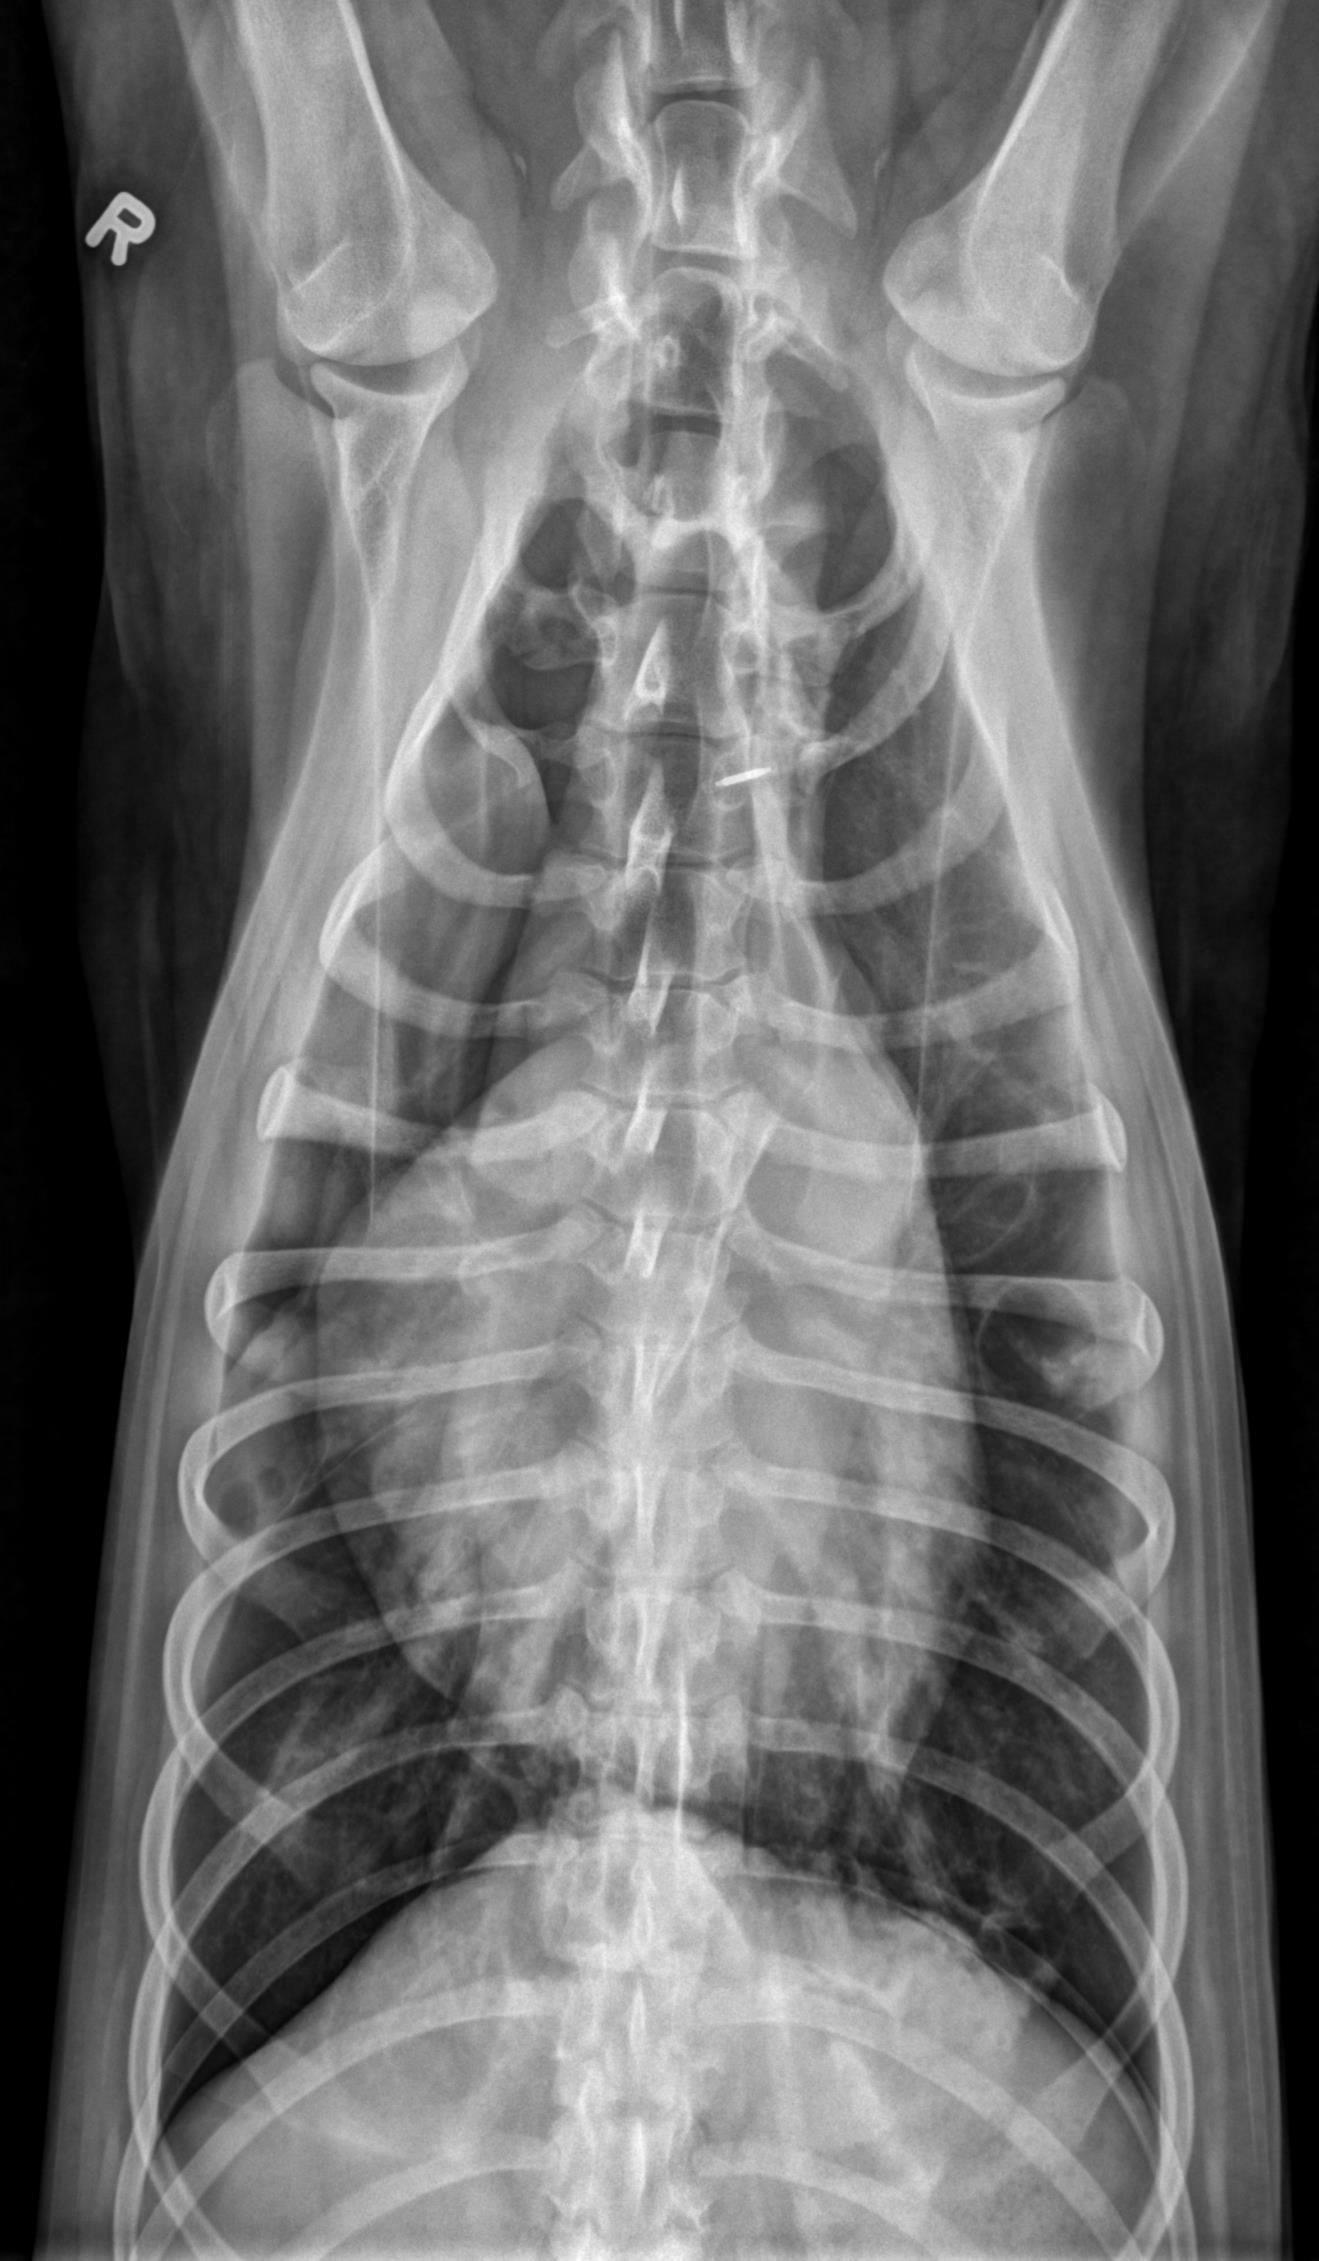

Thorax- ventrodorsal and opposite lateral radiographs are available for review.

There is a large volume of gas in the pleural space, bilaterally, with retraction of the pulmonary margins from the body wall. A smaller volume of fluid is also present. In the caudal subsegment of the left cranial lung lobe, there are two well-defined, gas filled structures with a thin, soft tissue opaque rim. The largest measures 2.7cm in diameter, and the smaller, located just cranial to the first measures 0.9cm in diameter. There is an alveolar pulmonary pattern in the ventral aspect of the right cranial lung lobe with an air bronchogram, most prominent on the left lateral projection. Throughout the remainder of the pulmonary parenchyma, there is a mild to moderate, diffuse, unstructured interstitial pulmonary pattern. Dorsal to the second and third sternebrae, there is an ovoid soft tissue structure consistent with an enlarged sternal lymph node (up to 1.6cm in thickness). The stomach contains a moderate volume of heterogenous soft tissue opaque material and gas. The musculoskeletal structures included in collimation are normal.

At least two pulmonary bullae. There is no reported history of trauma, and with the presence of at least two other pulmonary bullae, spontaneous pneumothorax secondary to ruptured bulla is possible.

Alveolar pulmonary pattern in the right cranial lung lobe may represent a focal region of more severe atelectasis (secondary to pneumothorax), however, given the history, underlying pulmonary pathology such as resolving pneumonia is also considered. The pulmonary pattern in the remainder of the lung lobes is consistent with atelectasis.

Mild to moderate sternal lymphadenopathy, likely reactive.

Gastric ingesta may be digestible or indigestible. Evidence of obstruction is not currently identified.